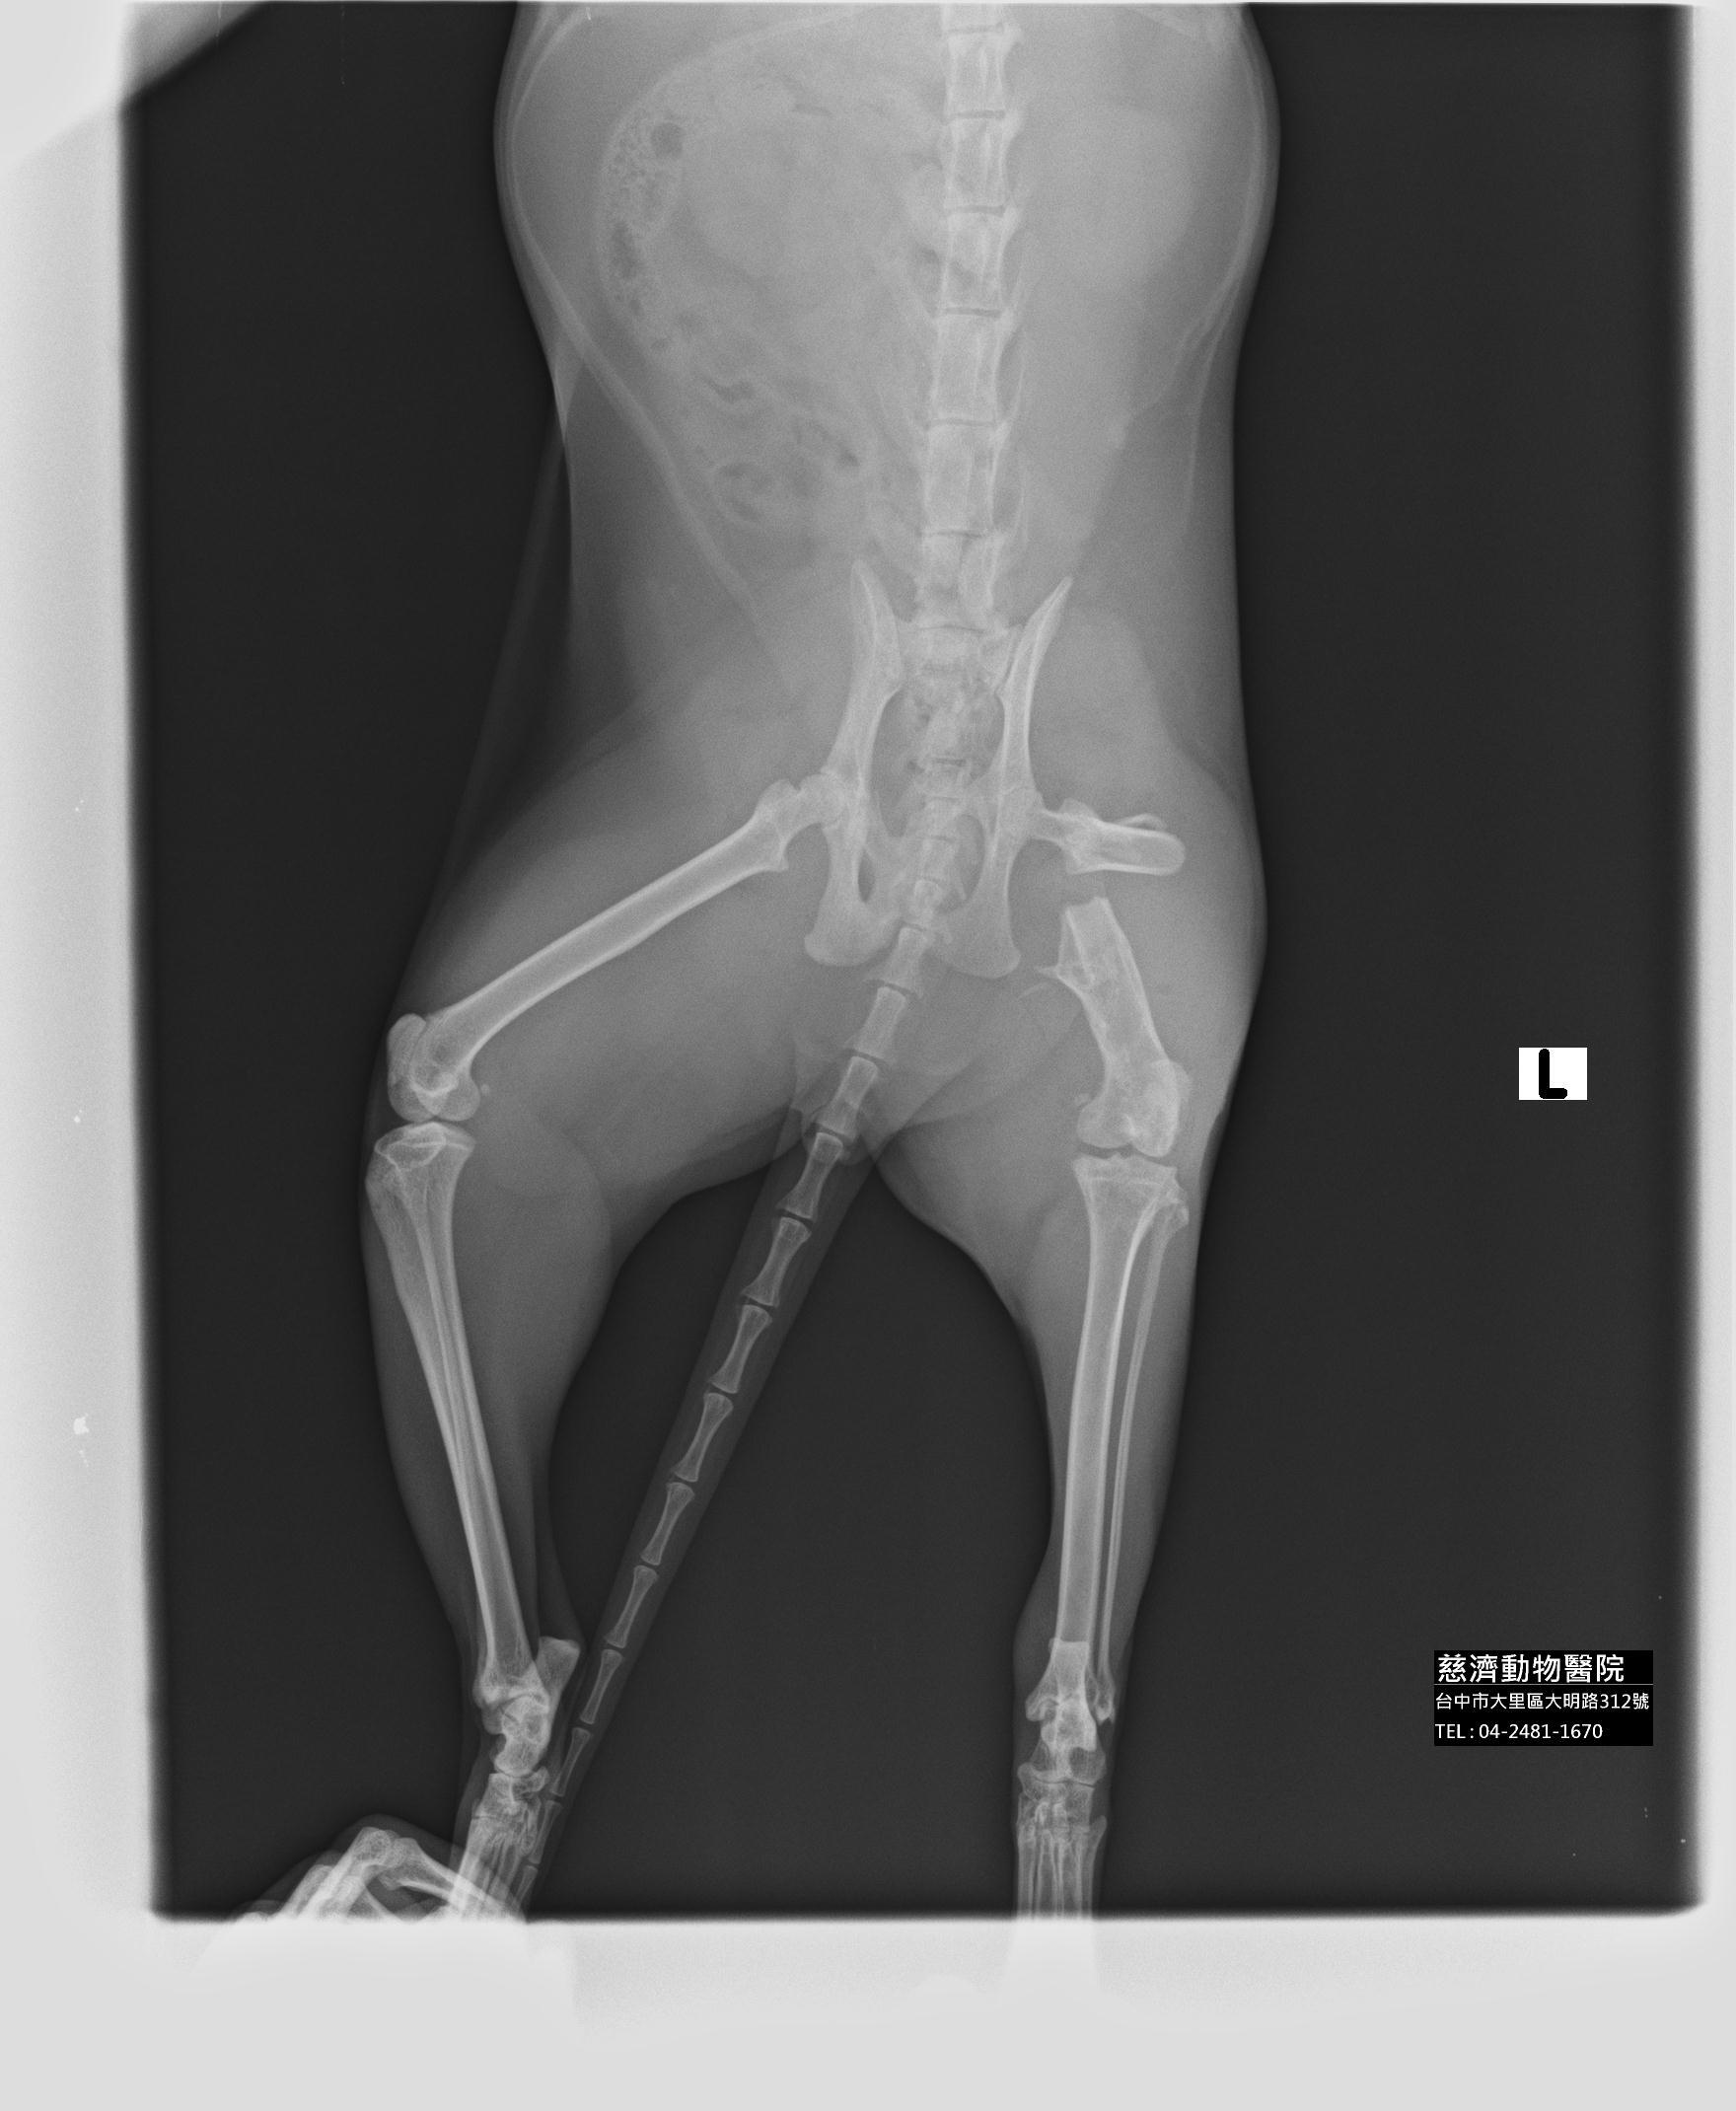

主題: 家門口食客喵喵腿再度斷掉 申請者姓名: 邱依如 花色: 申請日期: 2013-11-12 20:53:42 申請者部落格: 申請者臉書網址: 所在縣市/合作醫院: 台中市/慈濟動物醫院 治療費用: 15000元 需求人數: 17人 已結案 (2014-01-10 17:54:55) 報名人員: Bella(已付款)、鯉魚(已付款)、許韶娟(已付款)、蔡花枝 x2(已付款)、蔡花枝 x2、蔡花枝 x2、Patrick(已付款)、tau511(已付款)、Jason Chang(已付款)、ZLIN(已付款)、peggy(已付款)、momo(已付款)、小拉雅(已付款)、李坤財(已付款)、戴戴(已付款)、Jill Lee(已付款)、yuki x2(已付款)、 候補人員: 動物病情說明: 這隻喵喵是去年十月底曾經腿斷掉過申請醫助的浪貓

果不其然...原本斷掉的位置又斷掉了><

院長說喵喵本身骨頭就很脆弱(骨質酥鬆),所以會容易斷掉,這次手術完後真的要限制行動了><動物近況說明: 斷腿喵喵11/1出院了~狀況很好!!